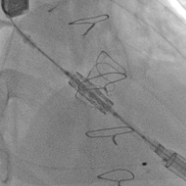

术前经详尽评估患者病情,通过CT重建测量瓣环直径、左室流出道面积。结合之前外科换瓣手术入路,最终决定采用经心尖途径行二尖瓣“瓣中瓣”手术,患者既往植入27#爱德华猪瓣,选用25# Renato®球扩式瓣中瓣。手术过程顺利,瓣中瓣植入位置理想,功能表现出色,左室造影及经食道超声观察无明显瓣中及瓣周反流。二尖瓣峰值流速由术前2.1m/s降至1.0m/s,平均跨瓣压差由7.2mmHg降至1.8mmHg。

瓣膜释放

瓣中瓣术后